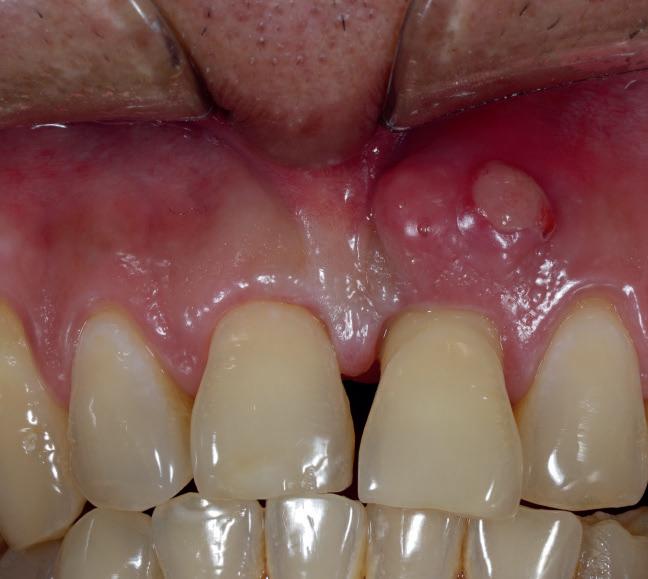

Rise of the Internet dental diagnosis

From the bizarre, and the ridiculous to the positively dangerous, online ‘dentistry’ has been blooming in popularity

It is hard to get an exact number of those who are regularly performing dentistry on themselves. However, in February, polling by the British Dental Association (BDA) revealed that 82% of dentists are treating gruesome cases of DIY dentistry. 2

Like a lot of the information that can be found on the internet, this advice may not be coming from a dental professional. At best, the advice may be useless. At worse, it could actually damage a patient’s teeth and gums.

Influencers are recommending rubbing fruit like strawberries and lemons on their teeth constantly to whiten them. Filing their teeth with a nail file so they look straighter. Using nail glue to fix their loose teeth to the gums.

These examples are certain to send a shudder of horror through any dental professional when their patients admit to attempting them. These types of DIY dentistry can cause permanent damage to patients’ mouths.

More importantly, these practices can cause pain and be costly to correct, putting pressure on the dentist to perform miracles and undo the damage.